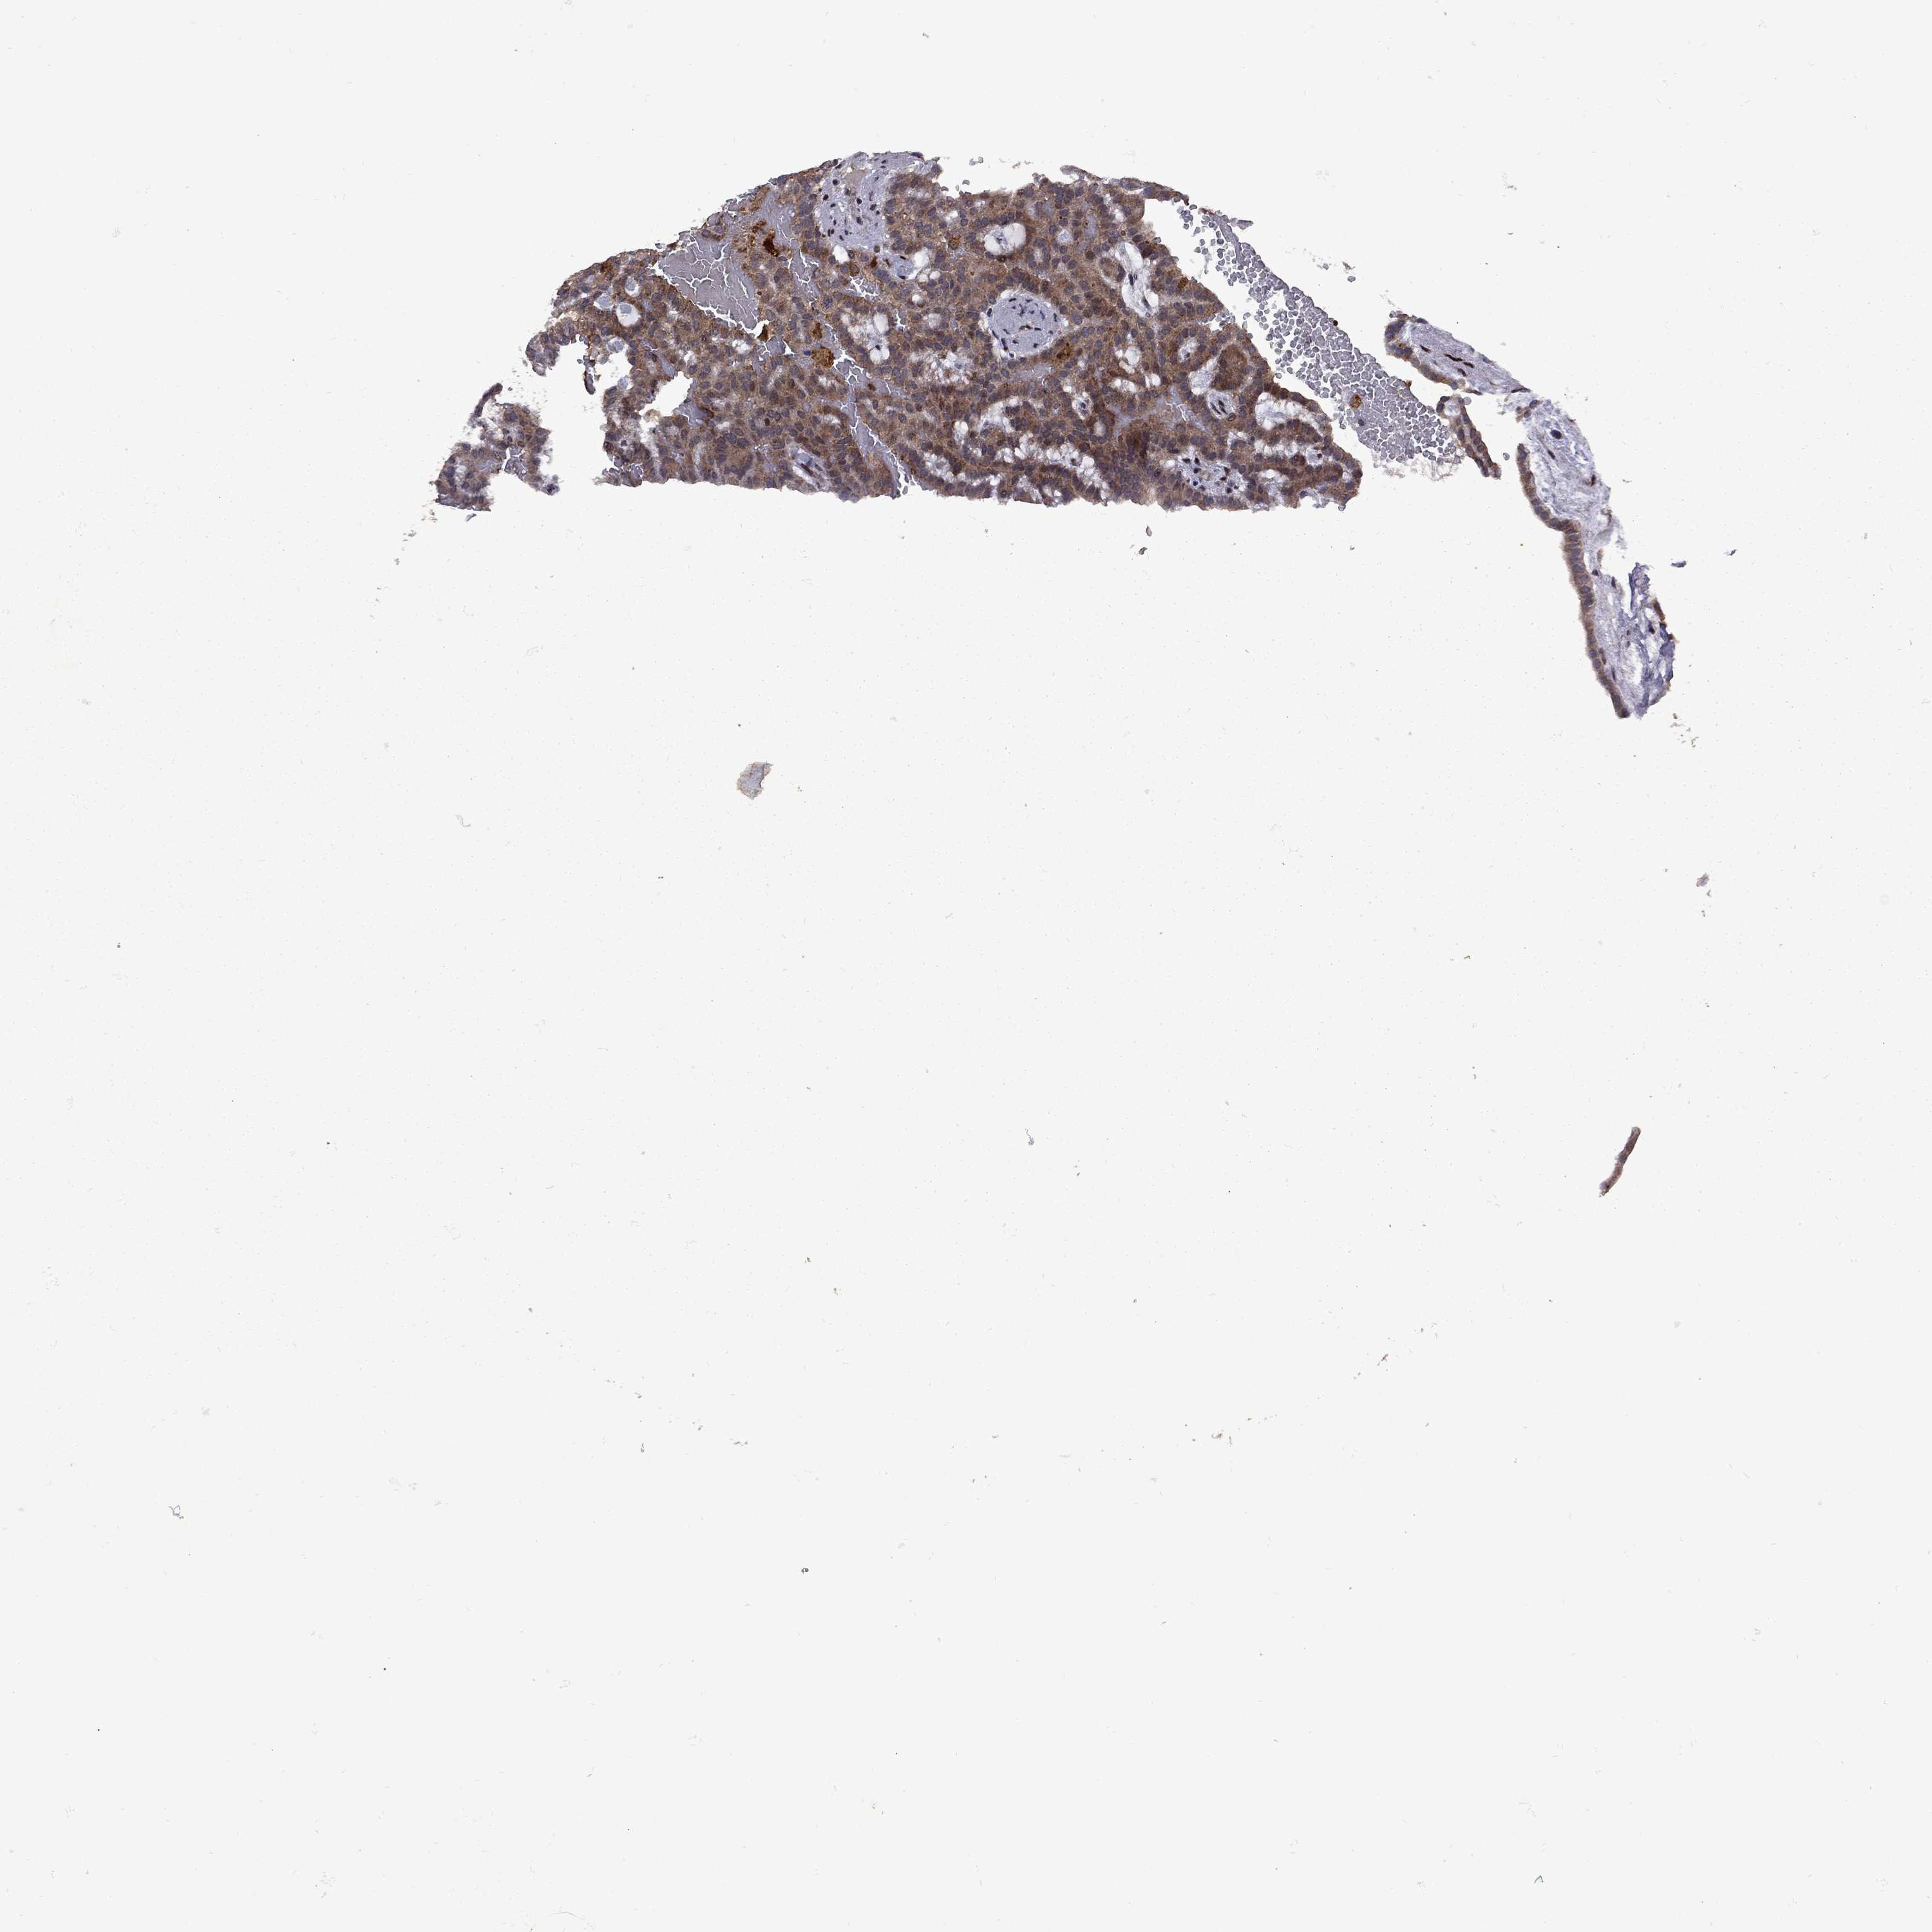

KIDNEY RENAL CLEAR CELL CARCINOMA (VALIDATION) - Interactive survival scatter ploti

The Survival Scatter plot shows the clinical status (i.e. dead or alive) for all individuals in the patient cohort, based on the same data that underlies the corresponding Kaplan-Meier plots. Patients that are alive at last time for follow-up are shown in blue and patients who have died during the study are shown in red.

IPP is validated prognostic, high expression is favorable in Kidney Renal Clear Cell Carcinoma (validation)

: 9.38

Average pTPM 7.6

Number of samples 100